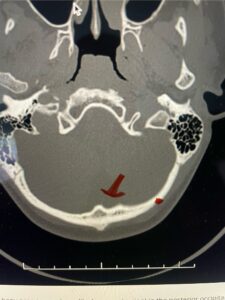

Fig. 6c: Axial cervical CT scan demonstrating a very thin right C2 isthmus (red arrow) compared to left side.